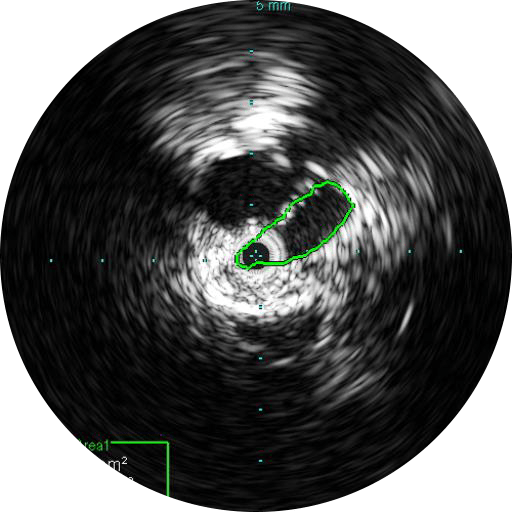

ВСУЗИ позволяет оптимальнее подобрать расходные инструменты, определить размер стента и морфологию сосудов.

Визуализация на 360 ̊ способствует лучшему пониманию заболевания и придаточных структур, к которым также относятся уровень компрессии, остеофиты, тромбы и прочее.

Цифровой катетер для ВСУЗИ Visions PV (0,035 дюйма) дополняет стандартные инструменты проведения ангиографических процедур, обеспечивая оценку морфологии кровеносных сосудов и их визуализацию в поперечном сечении. Благодаря рабочей длине, равной 90 см, и максимальному диаметру визуализации, равному 60 мм, для инвазивных процедур с использованием проводника диаметром 0,035 дюйма, устройство облегчает диагностику заболеваний вен и периферических артерий и помогает врачам выбрать правильный подход к лечению с учетом индивидуальных потребностей пациента.